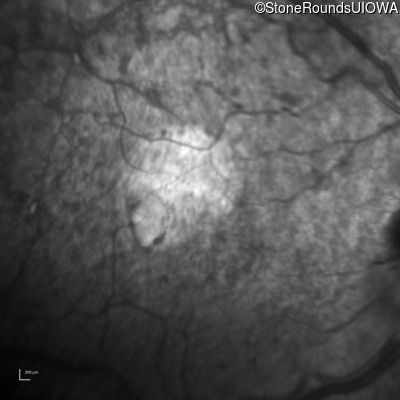

Infrared Fundus Photograph - Left - 20/500

Exemplar